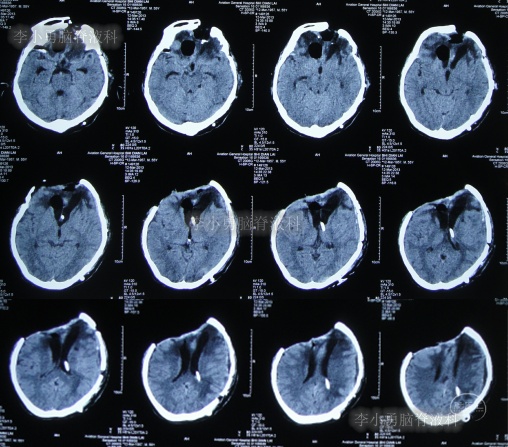

2013年1月22日(入院治疗83天),患者术区引流管引流液极少,复查头颅CT脑室较前稍有扩张,右侧骨窗张力仍较高(图-15),进行了侧脑室外引流术(右)+左额颞顶硬膜下引流管去除术+左顶硬膜外引流管去除术。

图-15:2013年1月22日头颅CT

2013年1月25日(入院治疗86天),查头颅CT示脑室有缩小(图-16)。

图-16:2013年1月25日头颅CT

2013年1月31日(入院治疗92天),查头颅CT示脑室进一步缩小,骨窗塌陷(图-18)。

图-18:2013年1月31日头颅CT

继续治疗1个半月,期间4次(2013年2月15日、2013年2月27日、2013年3月5日、2013年3月11日)查头颅CT(图-19、图-20、图-21、图-22)均示脑室在不断的变好。

图-19:2013年2月15日头颅CT

图-20:2013年2月27日头颅CT

图-21:2013年3月5日头颅CT

图-22:2013年3月11日头颅CT

2013年3月12日(入院治疗132天),拔除了头部外引流管(图-23)。

图-23:2013年3月12日头颅CT

2013年3月15日(入院治疗135天),查头颅CT示脑室周水肿减轻(图-24)。

图-24:2013年3月15日头颅CT